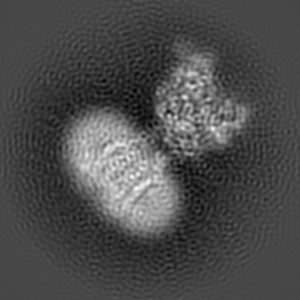

Cryo-EM structure of human GABA(B) receptor bound to the positive allosteric modulator rac-BHFF

Sample: Gamma-aminobutyric acid type B receptor

Fitted models: 7ca3